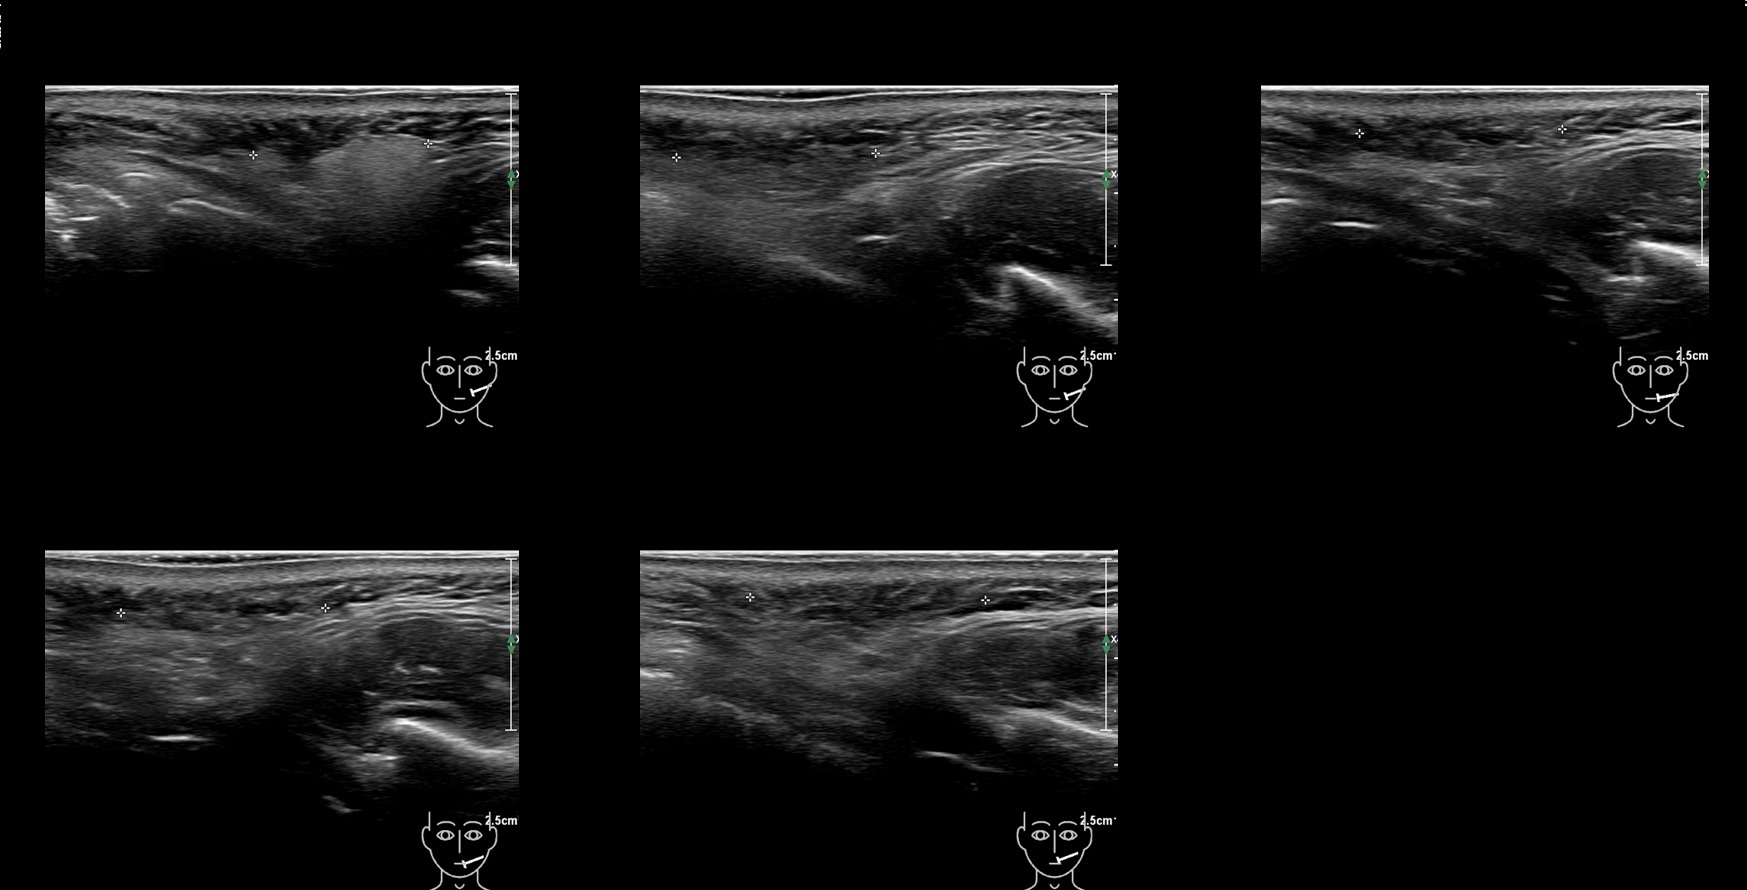

Fillers

Draw in the second image below where the fillers are located. To check if your answer is correct, swipe the first image to the right.